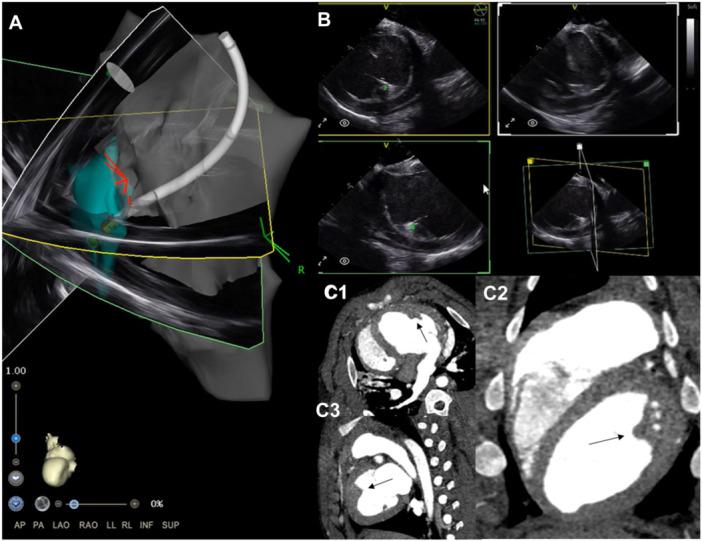

Intracardiac echocardiography (ICE) is an essential imaging modality for electrophysiology procedures, allowing intraprocedural monitoring, real-time catheter manipulation guidance, and visualization of complex anatomic structures. Four-dimentional (4D) ICE is the next stage in the evolution of the technology, permitting 360° rotation of the imaging plane, simultaneous multiplanar imaging, and volumetric acquisition, similar to transesophageal echocardiography (TEE). In this study, we report our experience with a novel 4D ICE catheter (NuVision, Biosense Webster) in structural electrophysiology procedures and difficult ventricular ablations in a swine preclinical model.

CARTOSOUND reconstruction was completed using the novel multiplane imaging software platform, allowing for creation of anatomy with minimal movement of the ICE catheter. Maps generated were similar to 3D reconstruction acquired in pre-procedure CT. Ablation lesions were successfully delivered to the LV papillary muscles and RV moderator band with excellent correlation between gross pathology, electroanatomic mapping (EAM), and ICE images. 2D, multiplane, and 3D volumetric images were obtained of the LAA with minimal catheter movement to simulate use for an LAAO procedure.

DISCUSSION

Intracardiac ultrasound has become an essential tool in the electrophysiology lab, especially for visualization of intracardiac structures in real time. 4D ICE is the natural progression of this technology, adding features previously only seen on TEE probes. In this preclinical study, 4D ICE was used to create CARTOSOUND shells with less catheter manipulation, which could decease procedural times and potentially decrease complications related to frequent manipulation of the ICE catheter. It was also placed in the left atrium to acquire multiplane and 3D rendered volumes of the left atrial appendage (LAA) similar to what would be required for an LAA occlusion procedure. This could be used as an alternative to TEE in LAAO procedures, potentially improving procedural efficiency and negating the need for general anesthesia. Additionally, it was used for real-time ablation guidance, specifically directly on the RV moderator band and LV papillary muscles. Multiplanar imaging allowed for more accurate catheter visualization and localization when targeting these complex 3D intracavitary structures.

心腔内超声心动图(ICE)是电生理手术中必不可少的成像方式,可进行术中监测、实时导管操作引导以及观察复杂的解剖结构。四维(4D)ICE是该技术发展的下一阶段,它允许成像平面进行360°旋转、同时进行多平面成像以及容积采集,类似于经食管超声心动图(TEE)。在本研究中,我们报告了在猪临床前模型中使用新型4D ICE导管(NuVision,Biosense Webster)进行结构电生理手术和困难心室消融的经验。

结果

使用新型多平面成像软件平台完成了CARTOSOUND重建,在ICE导管移动最小的情况下创建了解剖模型。生成的图谱与术前CT获得的三维重建图谱相似。成功地将消融灶传递至左心室乳头肌和右心室节制索,大体病理学、电解剖标测(EAM)和ICE图像之间具有良好的相关性。通过最小的导管移动获取了左心耳的二维、多平面和三维容积图像,以模拟用于LAAO手术。

讨论

心腔内超声已成为电生理实验室中的重要工具,特别是用于实时观察心腔内结构。4D ICE是该技术的自然发展,增加了以前仅在TEE探头中看到的功能。在这项临床前研究中,4D ICE用于以较少的导管操作创建CARTOSOUND模型,这可以减少手术时间并可能减少与ICE导管频繁操作相关的并发症。它还被放置在左心房中以获取左心耳(LAA)的多平面和三维渲染容积,类似于LAA封堵手术所需的容积。这可以在LAAO手术中用作TEE的替代方法,有可能提高手术效率并消除全身麻醉的需要。此外,它用于实时消融引导,特别是直接用于右心室节制索和左心室乳头肌。多平面成像在靶向这些复杂的三维心腔内结构时允许更准确的导管可视化和定位。